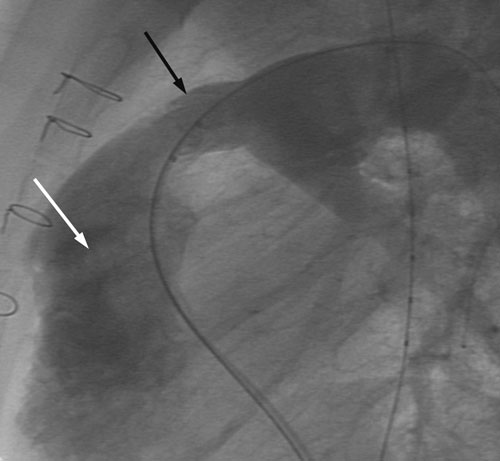

Kateteriseringsprosedyren blir gjennomført i samsvar med anbefalingene fra ledende internasjonale sentre og fra produsenten av perkutane kateterbaserte klaffer (7, 8). Pasientene er rutinemessig i generell anestesi under hele prosedyren, og det gis heparin intravenøst 100 IE/kg ved oppstart, etterfulgt av mindre påfyllingsdoser dersom prosedyren varer mer enn én time. Det gis antibiotika (Keflin 30 mg/kg) som en engangsdose. Det blir først foretatt en alminnelig høyresidig hjertekateterisering med tilgang fra lyskevene eller halsvene, trykkmålinger i høyre atrium, høyre ventrikkel og lungearterien, og angiografi med kontrastinjeksjon i høyre ventrikkel. Dette gir informasjon om stenose- og insuffisiensgrad i høyre ventrikkel-utløp, og også en detaljert anatomisk fremstilling av det området der den kunstige pulmonalklaffen skal forankres; sistnevnte har stor betydning for at prosedyren skal bli vellykket (fig 1). Med tilgang fra femoralarterie utføres dessuten koronarangiografi for å forsikre at koronararteriene ikke avklemmes når stenten plasseres i pulmonalutløpet.

Den kunstige pulmonalklaffen er fremstilt av halsvene fra kalv; klaffene i disse venene har en trikuspid anatomi som har stor likhet med humane pulmonalklaffer (8). Etter preparering i glutaraldehyd er venestump med klaff montert inn i en metallstent og forankret i denne med tallrike mikroskopiske suturer. Dette produktet (Melody, Medtronic, California, USA) kan komprimeres og føres inn i høyre ventrikkel-utløp gjennom et spesialdesignet kateter. Når rett posisjon oppnås, blir stenten med påsydd klaff ekspandert ved hjelp av ballonger slik at ytterveggene i stenten presses kraftig mot innsiden av høyre ventrikkels utløp. Dermed utvides utløpet, samtidig som stenten med klaff blir forankret. Trykkmålinger og angiografi etter innsetting blir brukt for å evaluere resultatet av prosedyren (fig 2). Alle stegene i denne prosedyren er utført i henhold til retningslinjer utarbeidet gjennom en serie europeiske møter gjennomført i regi av produsenten, og med deltakere fra alle de store sentrene i Europa. Vårt fagmiljø har bidratt aktivt i denne møteserien.

Innsetting av kunstig pulmonalklaff medførte signifikant lavere systolisk trykk i høyre ventrikkel hos samtlige pasenter; medianverdien ble redusert fra 60 mm Hg til 38 mm Hg (tab 3). Samtidig steg det diastoliske trykket i pulmonalarterien etter prosedyren hos et flertall av pasientene (tab 3, medianverdien er likevel den samme pga. liten spredning i materialet), og kontrastinjeksjon viste ingen eller minimal pulmonalinsuffisiens (fig 1 og 2). Median liggetid i avdelingen var to dager (maksimal liggetid fire dager for én person); pasientene ble deretter skrevet ut til hjemmet.